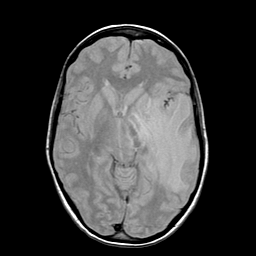

Metastatic bronchogenic carcinoma: proton density-weighted MR -- Slice #10

[Home][Help][Clinical] Slice 10